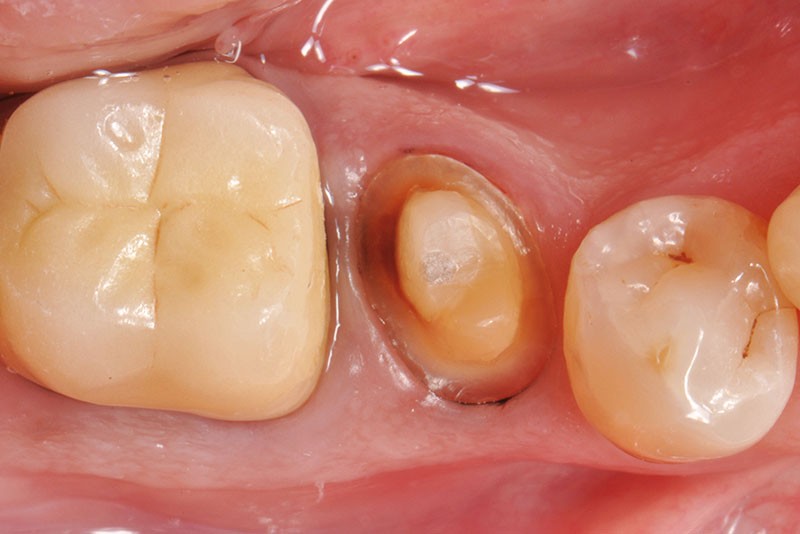

6. Après réalisation de la préparation périphérique externe, la hauteur, la largeur et l’épaisseur des parois résiduelles sont évaluées, ce qui permet de poser l’indication d’une RMIPP (reconstitution par matériaux insérés en phase plastique).